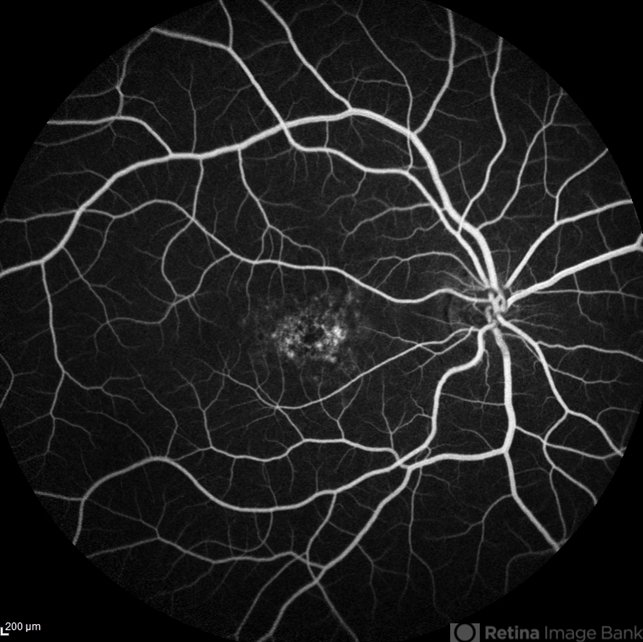

- Stargardt disease, choroid

- Kristen Dunn, North Texas Retina Consultants

- 24-year-old male with progressive decreased vision to level of 20/200 OU.